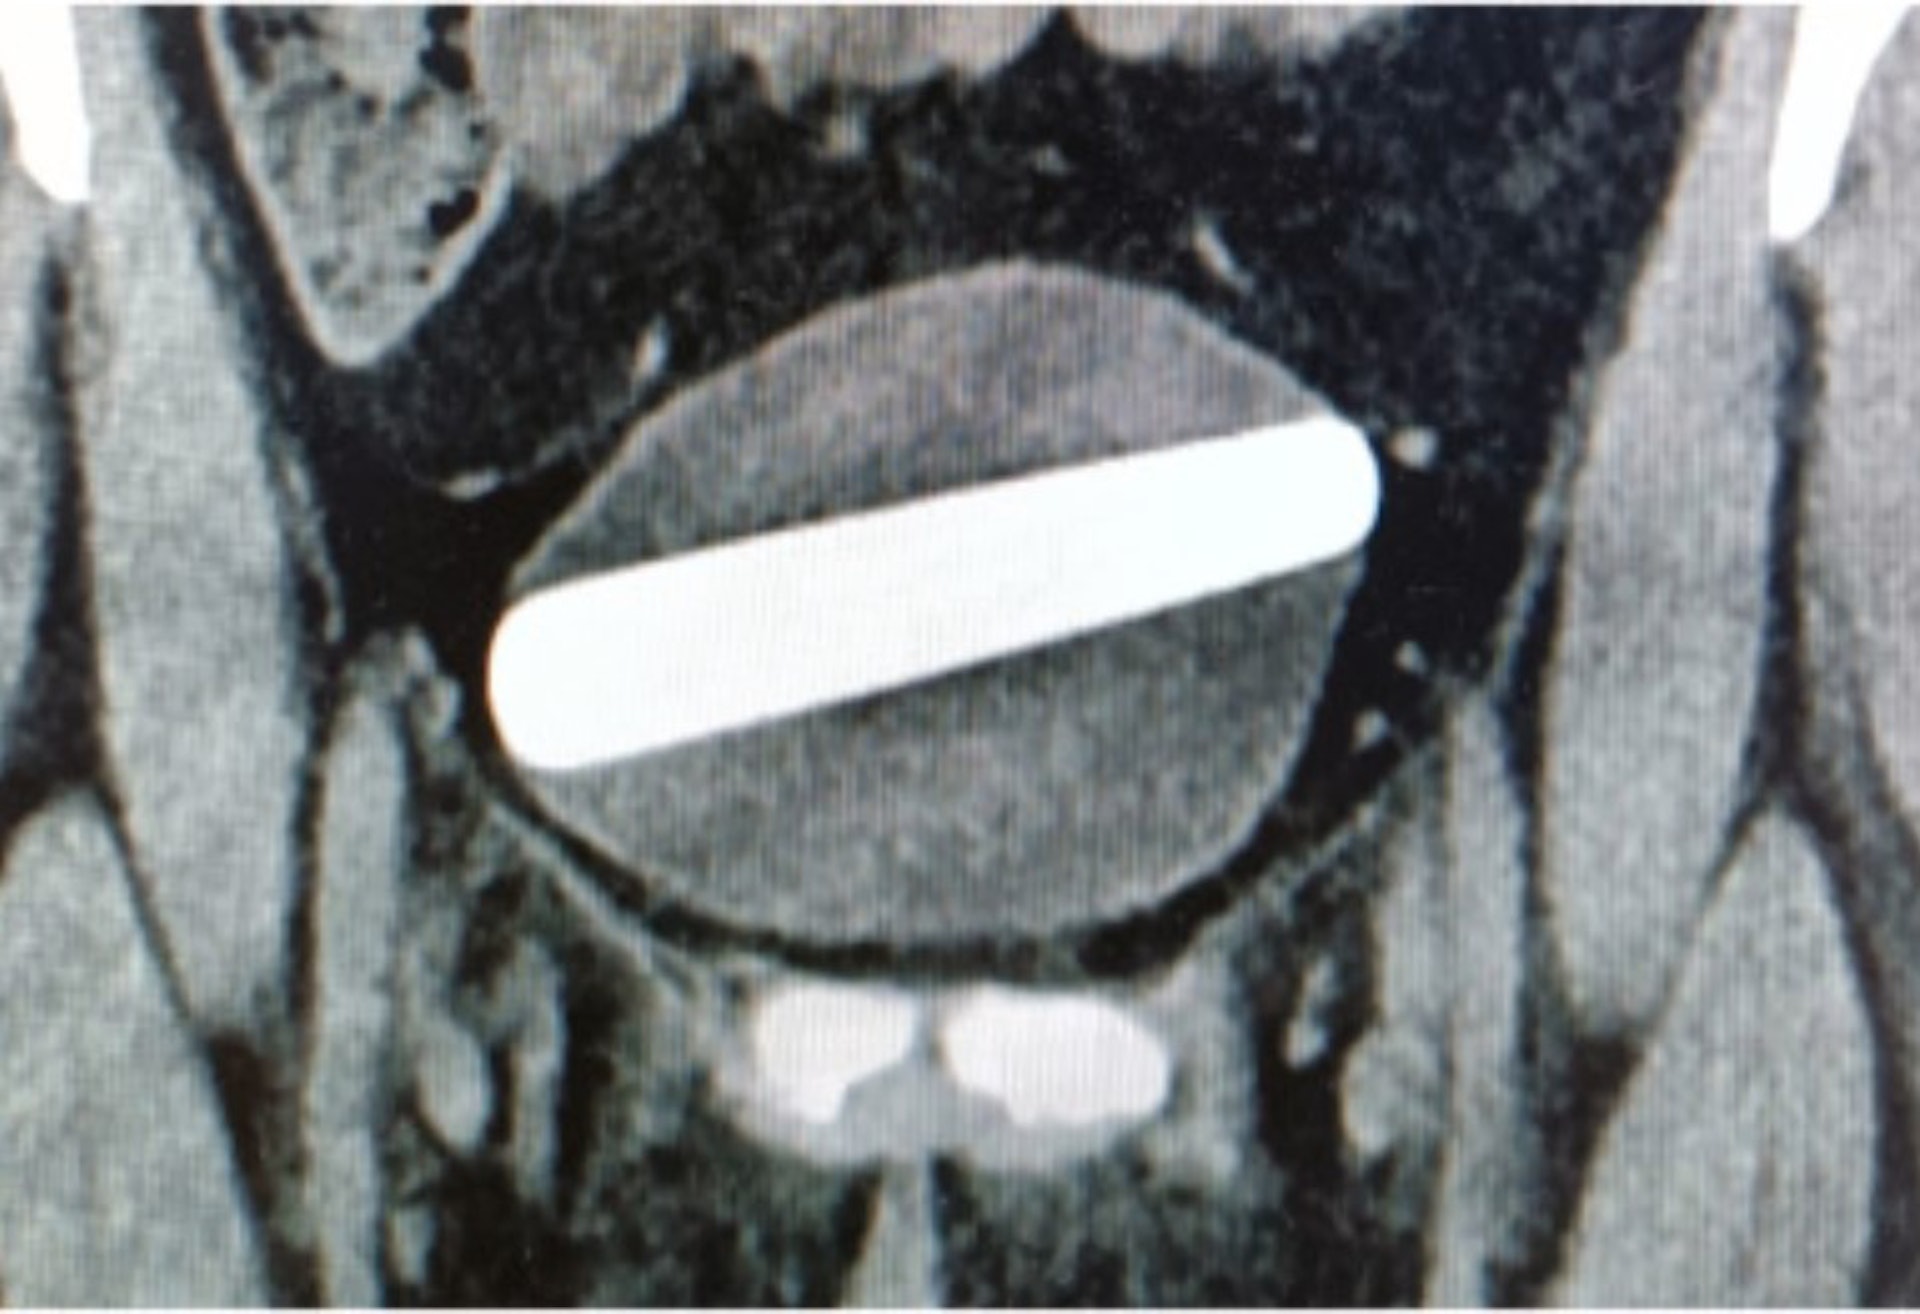

醫生利用超聲波初步窺見1個約10公分長的「長條狀異物」,及後透過盆腔X光掃描及CT掃描檢查,確認女子膀胱內有1根長9公分、寬2.5公分的異物,異物處於水平狀態卡在膀胱內,並擠壓着膀胱側壁。

以色列1名29歲女子誤將水晶假陽具塞入尿道,假陽具水平地卡在膀胱內,她嘗試取出不果,於是前往醫院求診。

(《泌尿外科病例報告》圖片)